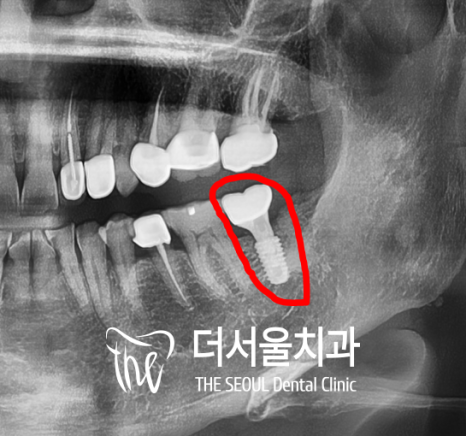

『세번째 수술

2022년 10월』

양주에서 오셨던 분이라 원거리 내원이죠?

그래서 저희 병원에 오시기전에 이미

어금니 통증에 따라서 타 병원에서

발치는 하고 오셨었습니다.

그래서 엑스레이에서 보실 수 있는 것 처럼,

빈 공간인 상태로 내원을 하셨었죠.

여기에도 뭐다?

똑같이 내비게이션임플란트 를

진행하게 되었었습니다.

여기에서는, 하악 골질의 불균형으로

식립 시 미끄러질 수 있다는 안내표시가 뜨네요.

여기에는 거의 2개월만에 지르코니아 크라운까지

완성시켜드린 것으로 기억합니다.